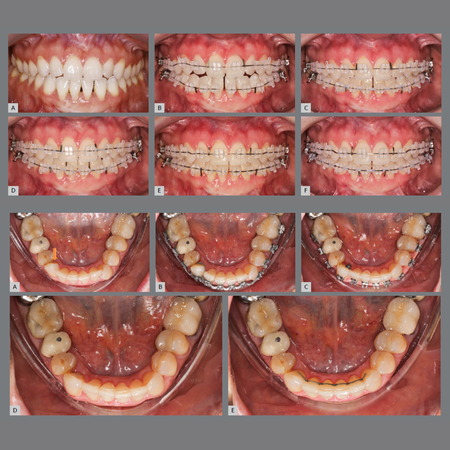

Leia maisIntroduction: Despite their aesthetic appeal and rising popularity, clear aligners face significant limitations in performing complex orthodontic movements such as anterior extrusion, severe rotations, and efficient molar distalization. These biomechanical challenges often result in longer treatment durations and reduced predictability. Objective: This article explores the hybrid treatment approach, which combines the biomechanical efficiency of fixed appliances in the initial phase with the...